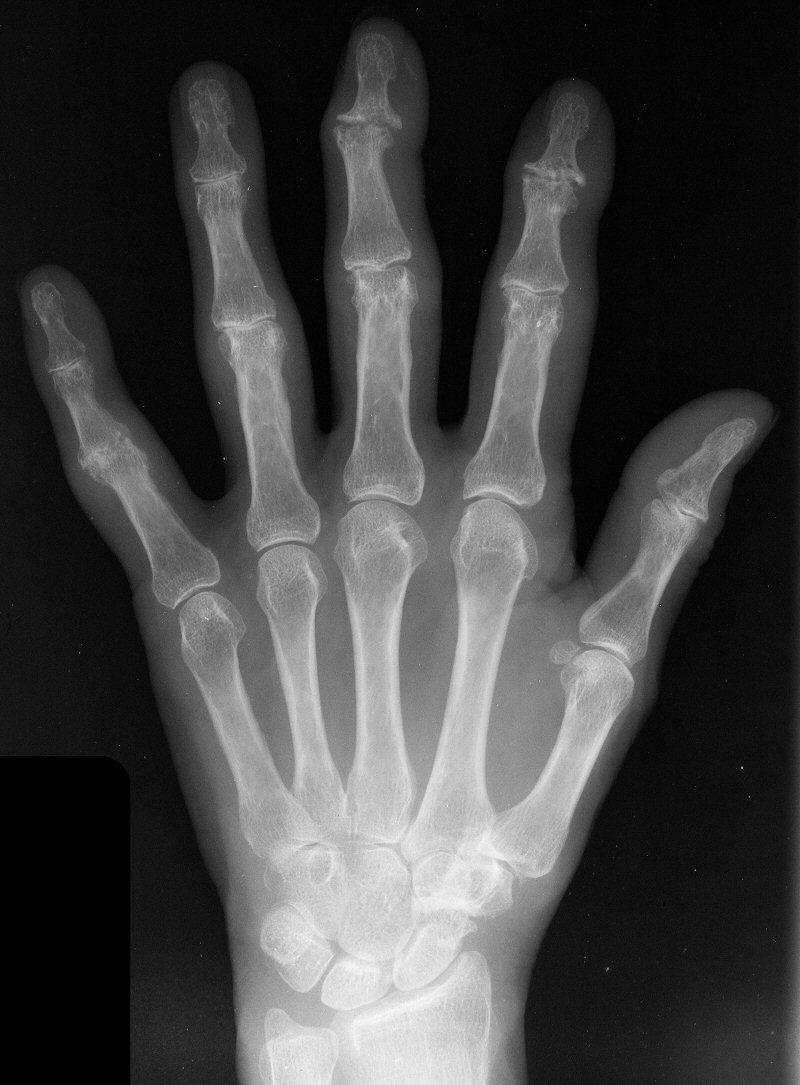

Clinical Example: Distal Interphalangeal Joint Arthroplasty with reversed Ascension carbon implant arthroplasty

These two cases illustrate the use of the Ascension PIP joint implant arthroplasty in the DIP joint position. The stem of the distal component is too wide to fit into the typical distal phalanx, but the proximal component stem will, and in selected cases, the implant will fit in this position if it is placed in a reversed proximal-distal position. These cases illustrate this technique - not as an endorsement, but as a demonstration of  technical feasibility. At one year, each  reconstructed joint was painless and had about 30 degrees range of motion.